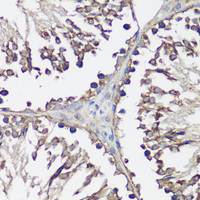

Immunohistochemical analysis of VAMP2 staining in rat testis formalin fixed paraffin embedded tissue section. The section was pre-treated using heat mediated antigen retrieval with sodium citrate buffer (pH 6.0). The section was then incubated with the antibody at room temperature and detected using an HRP conjugated compact polymer system. DAB was used as the chromogen. The section was then counterstained with haematoxylin and mounted with DPX.